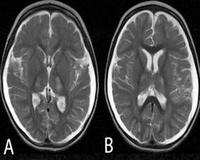

- МРТ головного мозга. На снимках визуализируются зоны умеренного гиперинтенсивного сигнала в затылочных областях церебральной коры. Для резистентных приступов характерно появление участков повышенной интенсивности в таламусе, продолговатом мозге. В базальных ганглиях, стволе мозга и мозжечке визуализируется прогрессирующая атрофия.